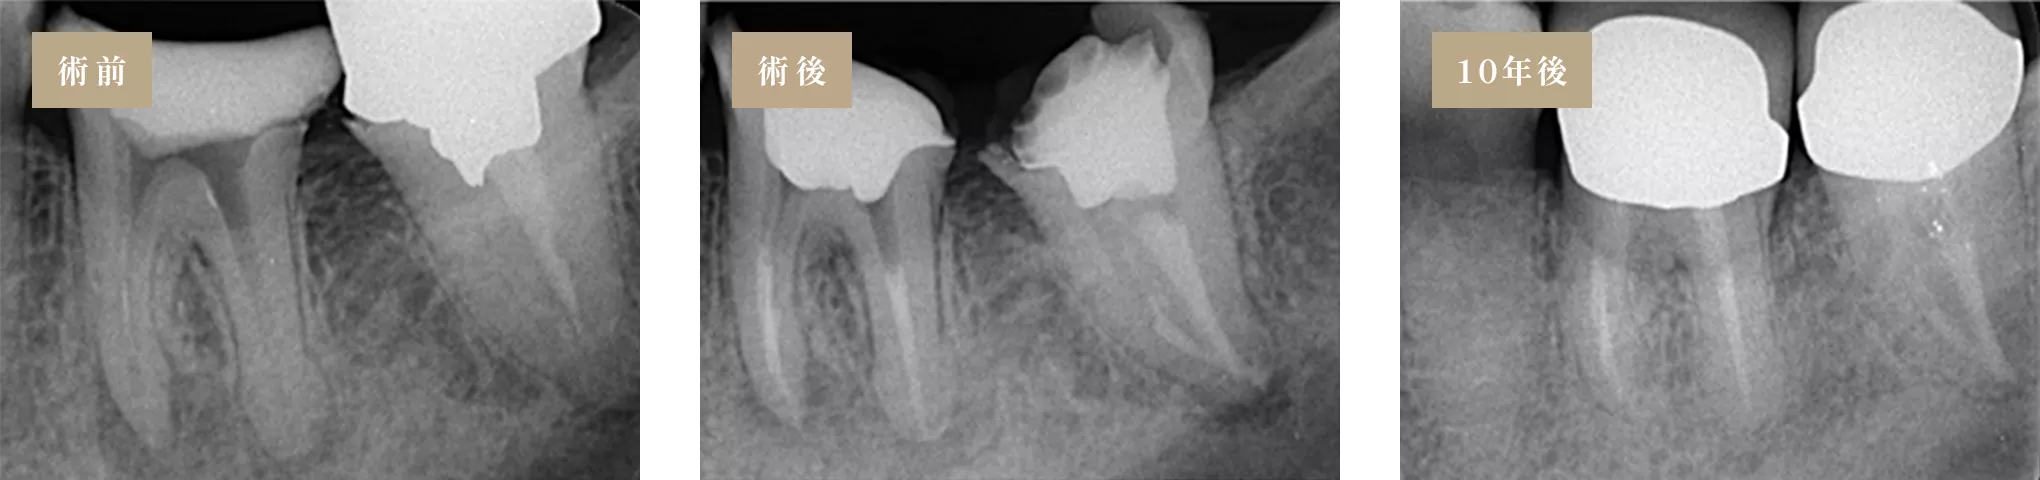

「抜歯しかない」と診断されても、適切な診断を行い、

歯の状態を正しく見極めることで、歯を残せるケースは決して珍しくありません。

実際に、抜歯と判断された歯でも、適切な治療によって保存できる可能性は十分にあります。